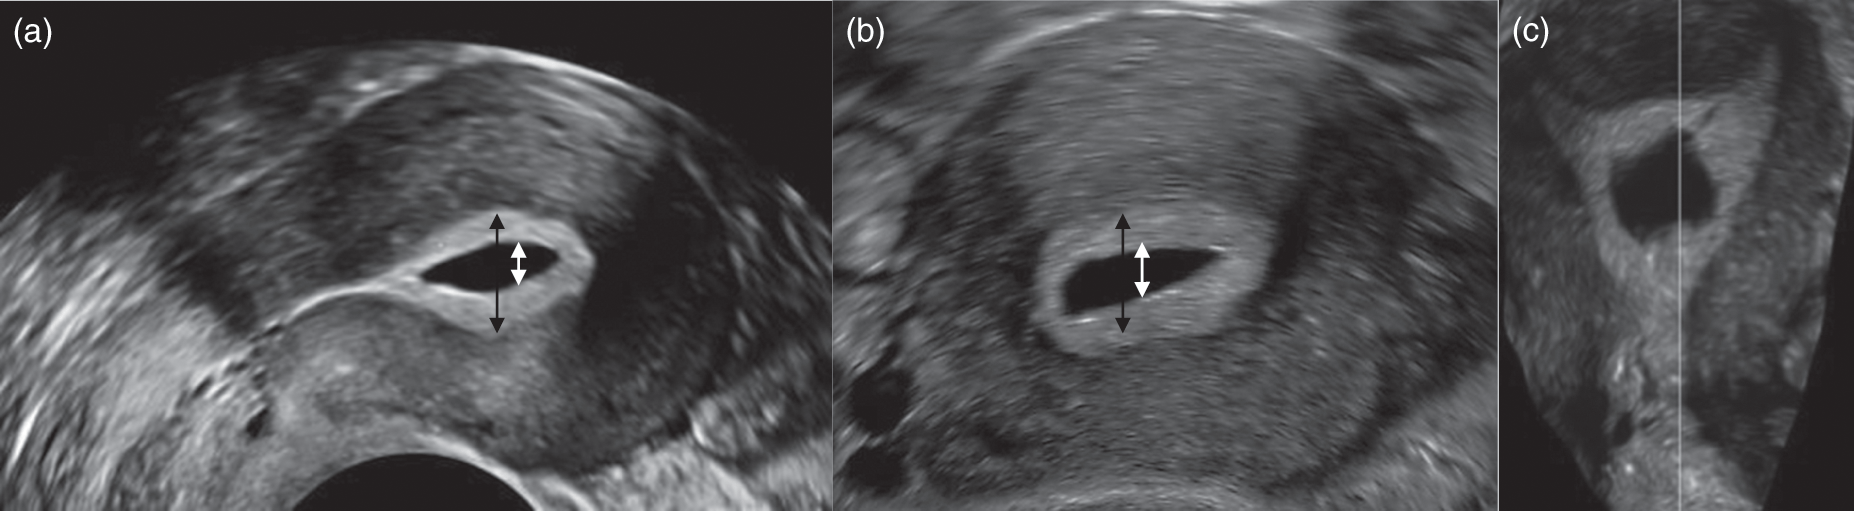

宫腔积液 试管移植